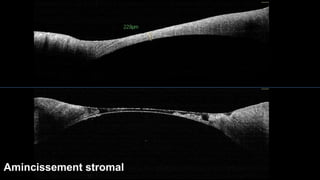

Amincissement stromal